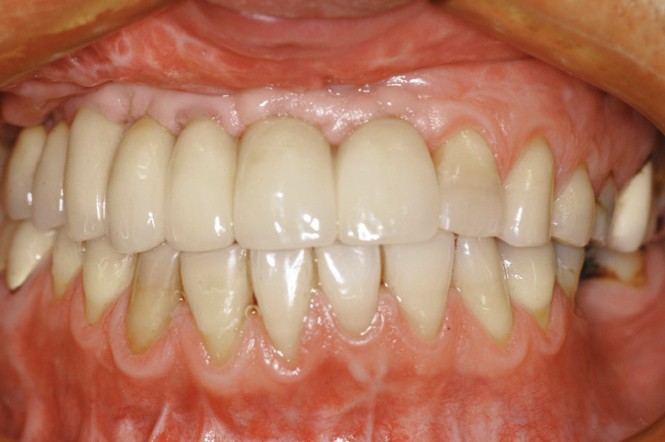

Car ce sont bien des situations cliniques exceptionnelles que ce conférencier a prises en charge, non pas seul, mais en constituant une équipe multidisciplinaire plus à même de relever les défis fonctionnels, structurels, biologiques et esthétiques en présence. Après avoir passé en revue les composants essentiels à l’obtention d’un sourire équilibré, Nadim Aboujaoude a évoqué les travers des traitements dits esthétiques mais conduits sans planification globale et qui engendrent des résultats disgracieux. Depuis de nombreuses années, l’engouement pour les solutions esthétiques ne faiblit pas. La divulgation médiatique des progrès technologiques et chirurgicaux réels encourage une part croissante de la population à recourir à des procédures souvent fiables, mais parfois portées au-delà des limites raisonnables. Ainsi, des traitements de médecine esthétique inadaptés engendrent un effet de « ligne de sourire basse » accompagné d’une exposition exagérée des incisives mandibulaires.

La demande de correction de cette anomalie esthétique incite les patientes à rechercher une compensation prothétique (à travers un abaissement des bords incisifs maxillaires visant à rendre sa visibilité au groupe incisivo-canin maxillaire) qui concoure à recomposer les rapports des étages de la face (en minorant l’étage inférieur et majorant l’étage moyen). La reprise de ces cas cliniques se révèle particulièrement délicate et repose sur une analyse rigoureuse des clefs esthétiques de l’harmonie du sourire et de son rayonnement au sein du visage.

Concernant le versant orthodontique des traitements multidisciplinaires, Nadim Aboujaoude intègre cette thérapeutique moins invasive à ses traitements multidisciplinaires sans rechercher une occlusion de classe 1 mais en privilégiant l’obtention de situations facilitant les solutions prothétiques, parodontales ou implantaires : en redistribuant et optimisant les espaces prothétiques, en corrigeant les malpositions dentaires, en remplaçant les dents compromises par les dents adjacentes, en harmonisant les contours gingivaux, en optimisant l’inclinaison des racines dentaires et en créant des volumes osseux favorables à la mise en place d’implants. À l’issue d’une présentation riche en prise en charge thérapeutique de cas complexes, le conférencier a clairement démontré que toute solution thérapeutique ne peut se concevoir et s’établir que dans une logique multidisciplinaire axée sur la concertation.